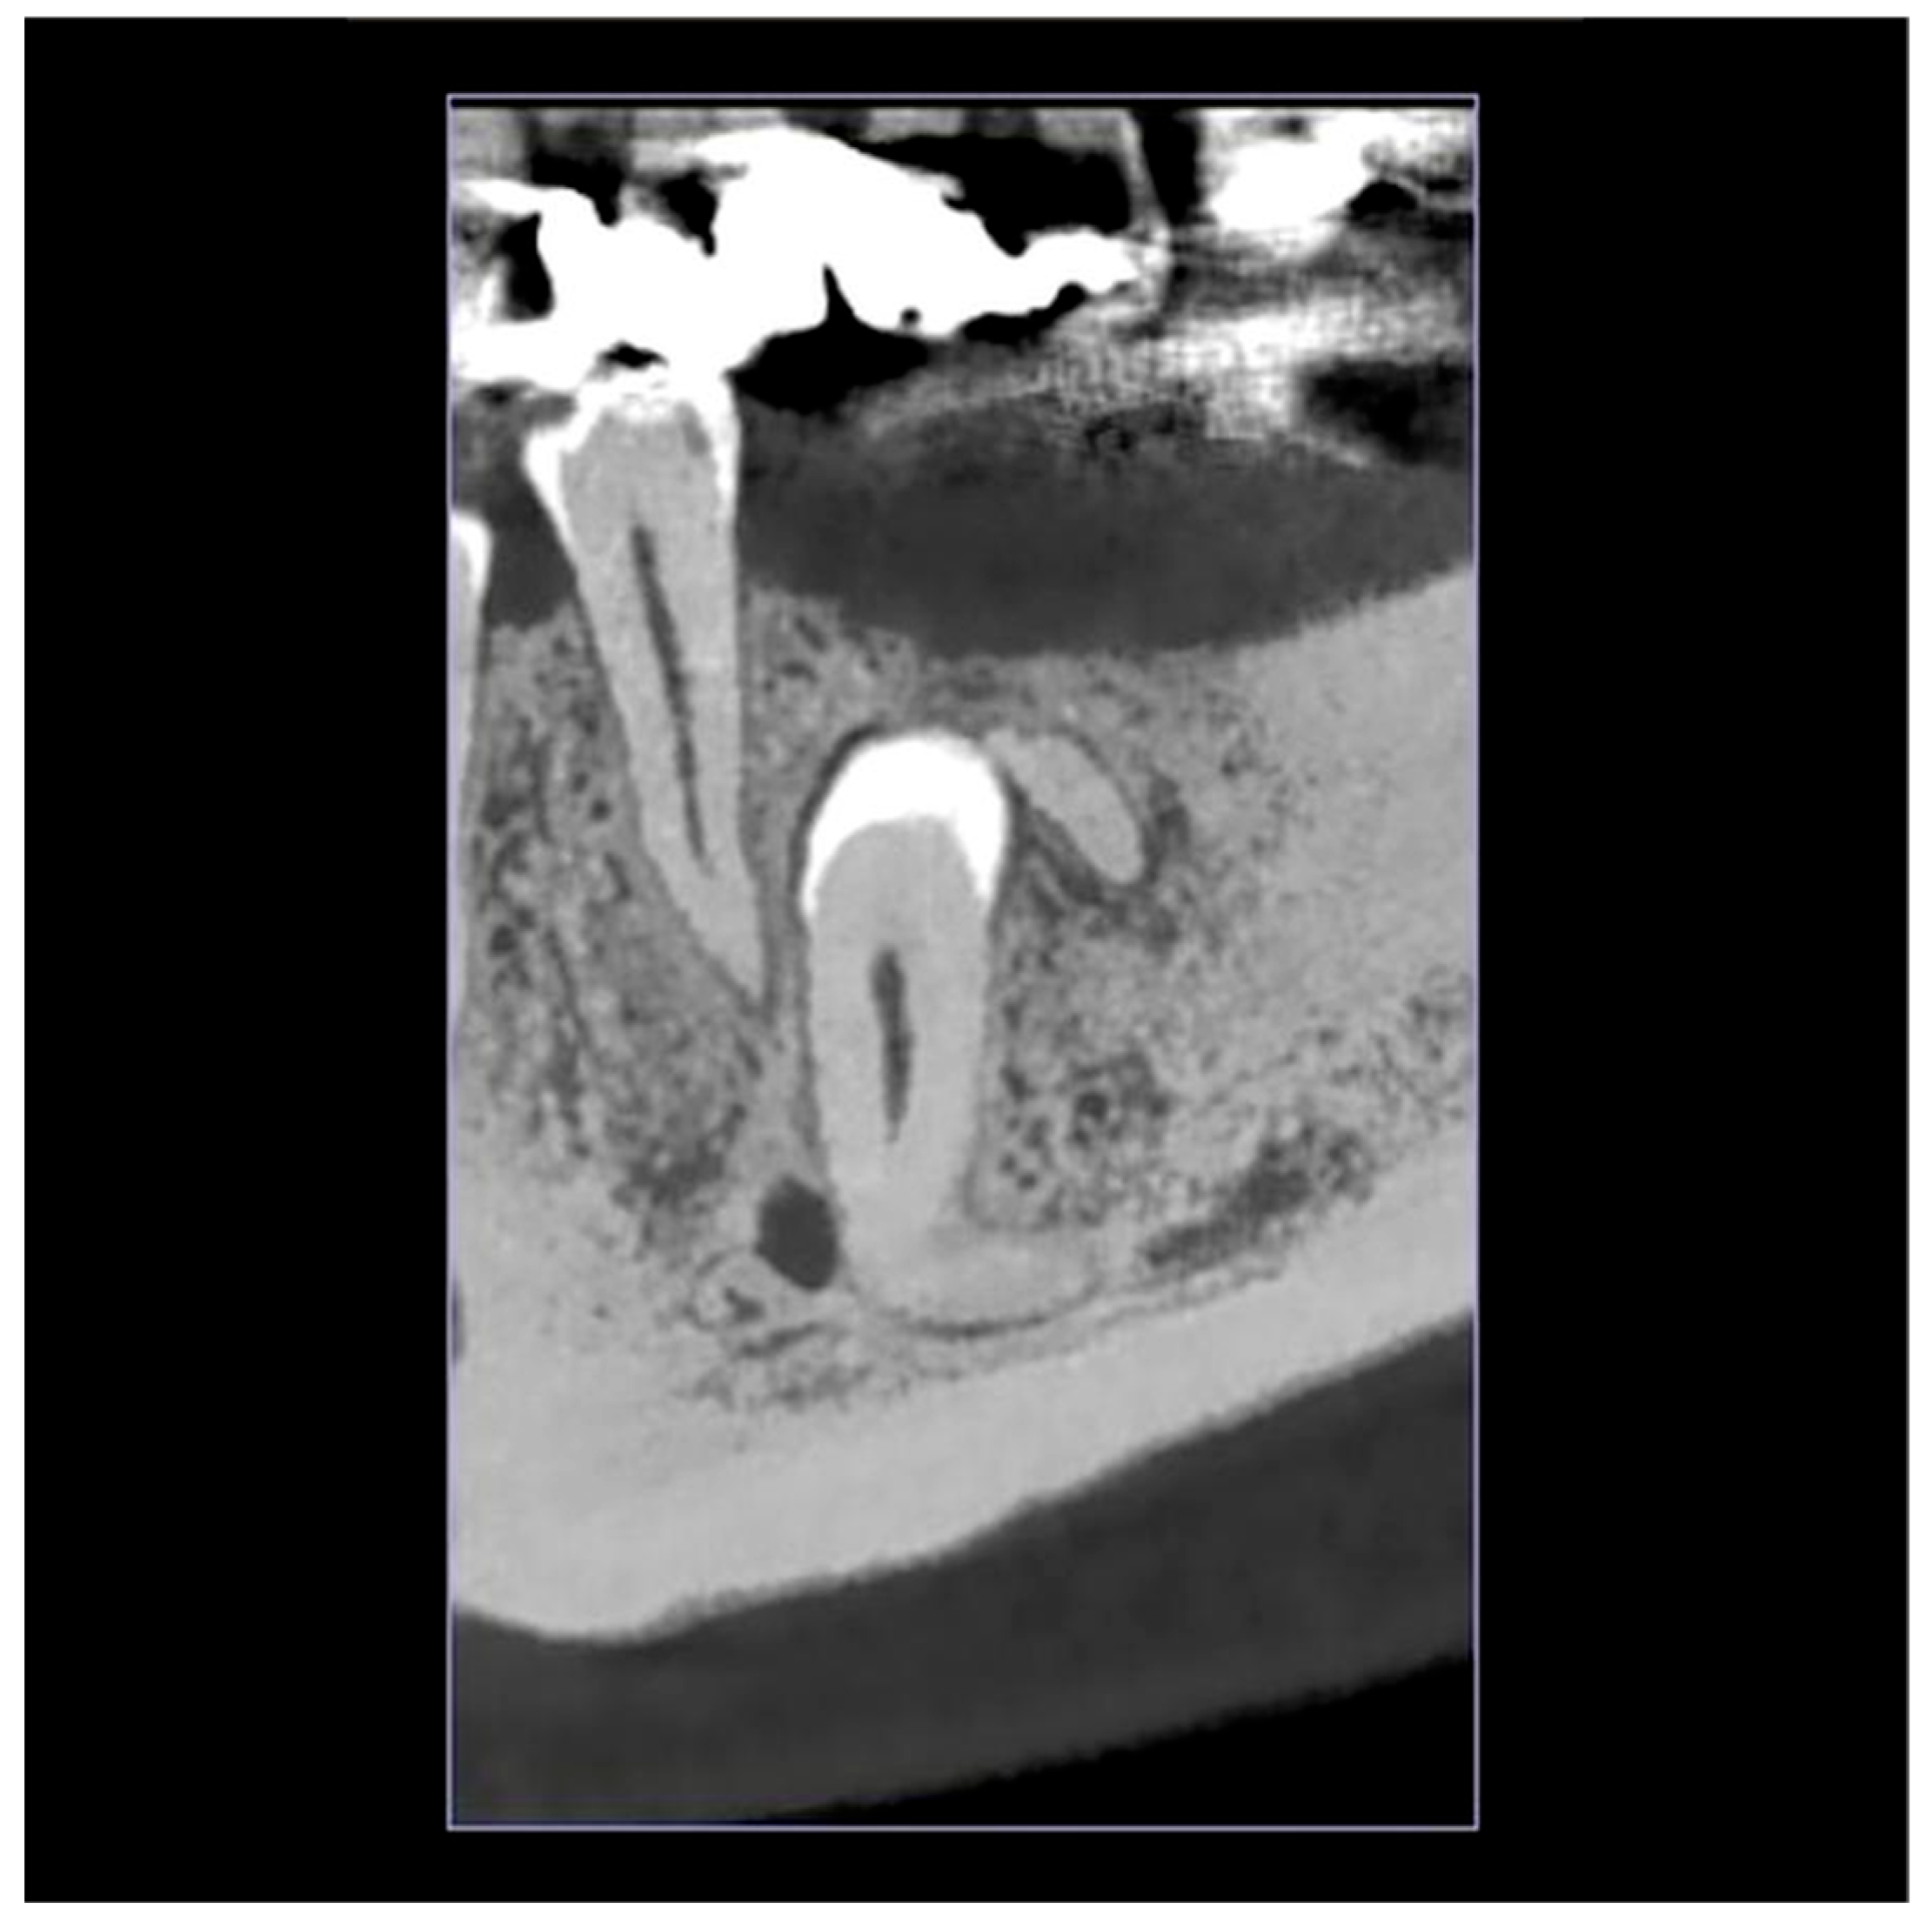

2.1. Initial Visit, Radiographic Evaluation and Diagnosis

2.2. Surgical Intervention